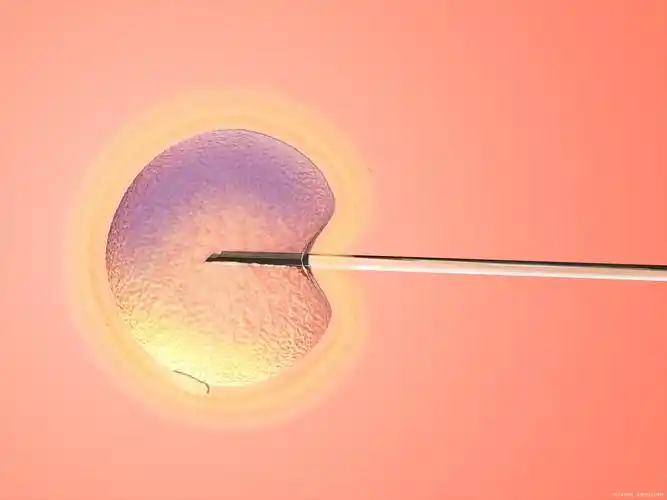

当然,试管婴儿治疗也需要提取精卵来完成体外受精。由此,我们应该清楚地发现,即使选择试管婴儿辅助怀孕,对身体也是有要求的,尤其是生育能力和卵巢功能,还是需要一定的条件。